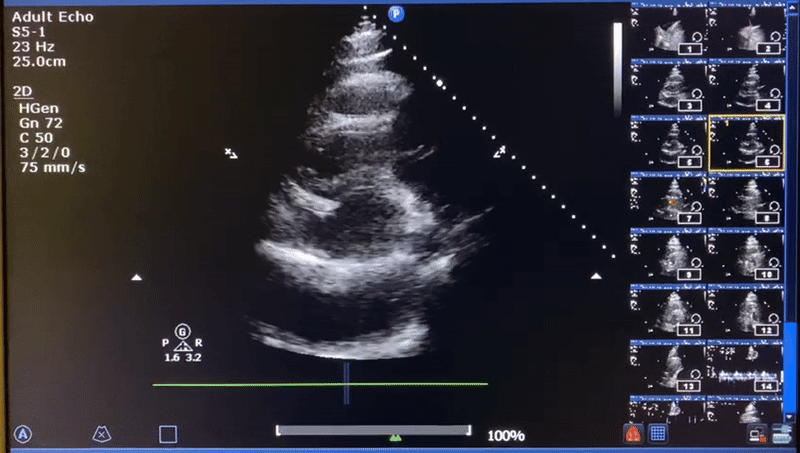

The name of this sign

14

1 pts

The potentially life-threatening finding here